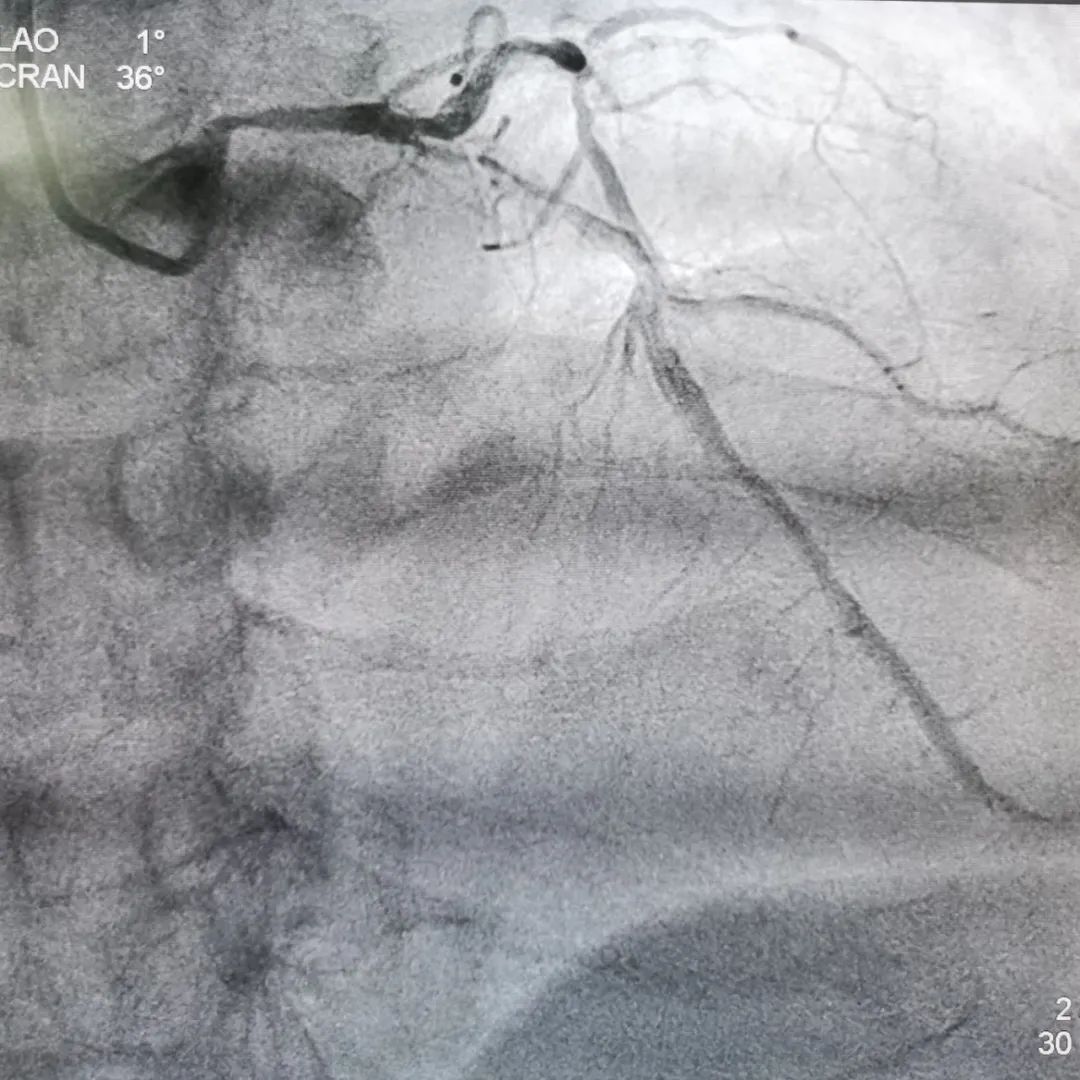

以右侧桡动脉为入径,置入APT 7F桡动脉鞘管,5F TIG多体位投照下行冠脉造影。冠脉造影示:冠脉呈右优型,LM偏心狭窄,全程弥漫狭窄,前降支近段重度钙化并弥漫狭窄达95%,血流TIMI 2级;LCX远段慢性闭塞;RCA中段原药物球囊治疗处残余狭窄小于20%。

冠脉造影最终结果